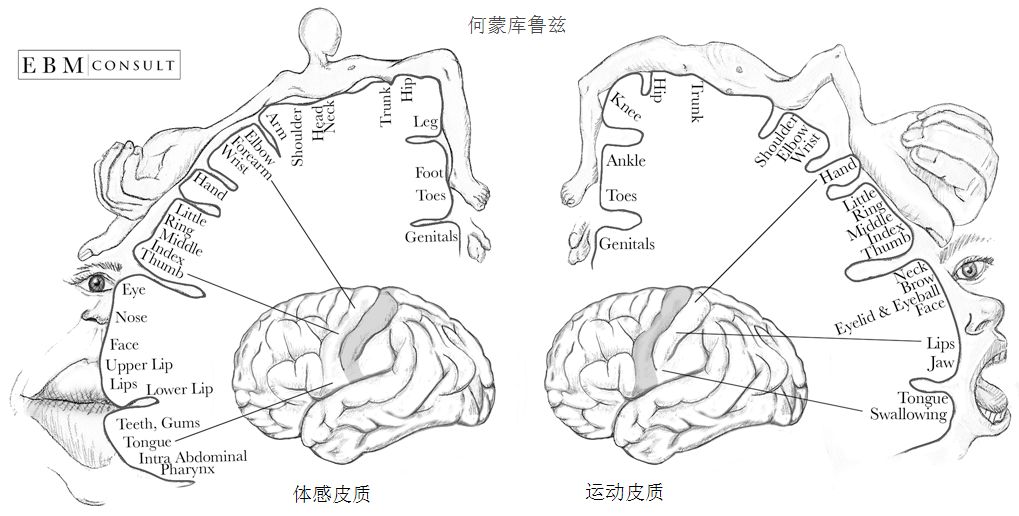

运动和体感皮质很有趣,因为它们和人体的对应关系非常工整。神经科学家清哪楚地知道每个皮质的各部位分别对应身体的那些部分,下面我们要放出本文中最奇怪的一张图:何蒙库鲁兹(homounculus)

何蒙库鲁兹由神经外科医生Wilder Penfield创造,用来呈现运动和触感皮质如何对应到人体部位。图中的人体部位越大,代表运动和触感皮质中有越多的部分是与该部位对应的。这张图有一些有趣的点:

首先,皮质中负责脸和手的运动和触感的部分,比全身其它部分加起来都要大。当然这不难想通,人脸需要能做出各种微妙的表情,而手需要能够无比的灵巧。而身体的其它部位,比如肩膀、膝盖、背部,在移动和触感上可以粗糙很多。所以人们用手指,而不是脚趾,来弹钢琴。

其次,运动和触觉皮质各自对于不同身体部位的分配比例基本是一致的。也就是说人体中越是需要灵活运动的部位,也越是触觉最灵敏的。

最后,如果我们把何蒙库鲁兹3D化的话,它应该长这样: